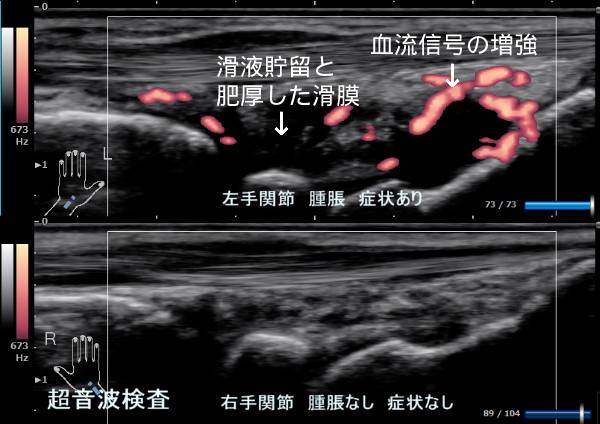

2つ目が、超音波検査です。

関節同士がぶつかることで出来る骨棘(コツキョク)が確認できます。

また、関節リウマチでは炎症がありますが、ヘバーデン結節やブシャール結節では炎症がありません。

軟骨が磨り減ったり、骨棘が出来ることで、骨同士が当たることで、関節の痛みが出てきます。